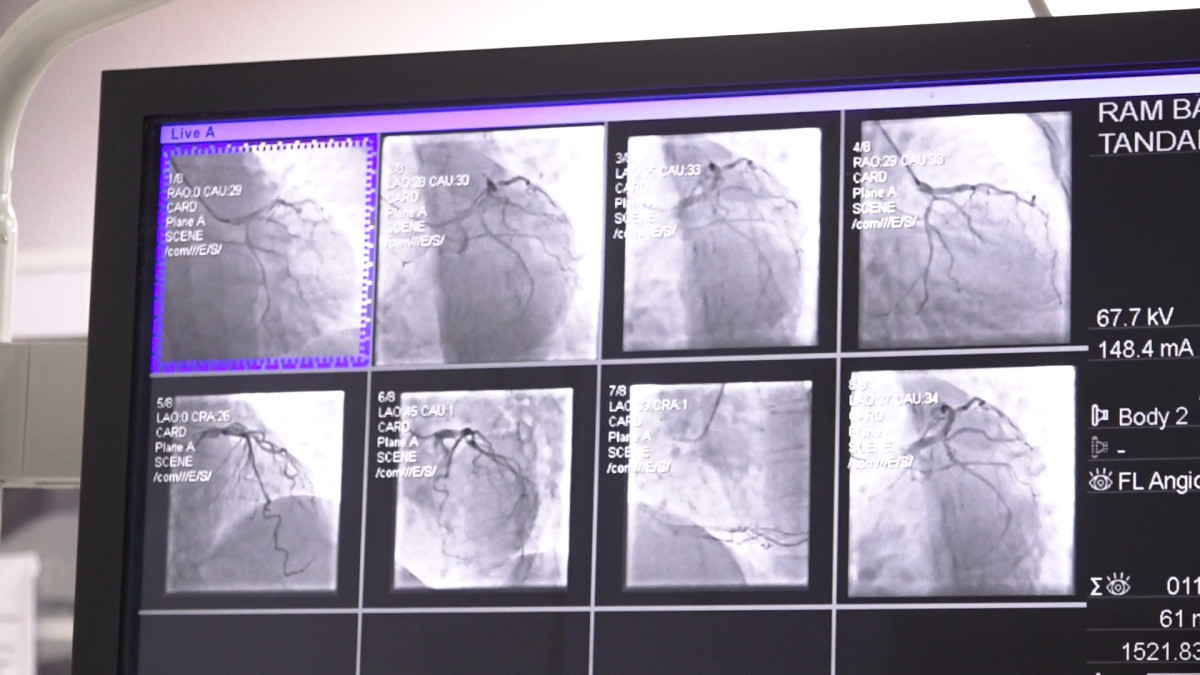

प्रा. ढुङ्गानाकाअनुसार क्याथ ल्याव एक विशेष प्रकारको अत्याधुनिक एक्स–रे मेसिन हो । जसले धड्किरहेको मुटु र नशागत समस्याहरूको जाँच तथा उपचार गर्न सकिन्छ । डा. ढुङ्गानाले क्याथ ल्यावमा हृदयको नशा परीक्षणका लागि हात वा खुट्टाको नशामा सानो सुई (सामान्यतः स्थानीय एनस्थेसिया) मार्फत पाइप (क्याथेटर) प्रवेश गराइने बताउनु भयो । यो प्रविधिमार्फत हृदयका विभिन्न रोगहरू—जस्तै नशा ब्लकेज, जन्मजात मुटुका प्वाल, भल्बको साँघुरो वा अन्य हृदयसम्बन्धी जटिलताहरूको छिटो र सुरक्षित उपचार सम्भव भएको प्रा. ढुङ्गानाले बताउनु भयो । यस प्रक्रियाले धेरै जटिल रोगहरूलाई सहज र सुरक्षित बनाएको उहाँले जिकिर गर्नुभयो ।

बाइ–प्लेन प्रविधिः दुवै फोटो एकैचोटि

काठमाडौं मेडिकल कलेजले प्रयोग गर्दै आएको क्याथ ल्याव ‘बाइ–प्लेन’ मोडेल भएकाले यस प्रविधिले एकैचोटि दुईवटा फोटो खिच्नसक्ने जसका कारण डाई र विकिरणको मात्रा कम हुने डा.ढुङ्गानाले बताउनु भयो । उहाँकाअनुसार ‘यसले बिरामीको मिर्गौलामा पर्ने प्रभाव घटाउँछ र चिकित्सकको काम पनि सहज बनाउँछ’ । नेपालमा करिव एक दशक अगाडि भित्रिएको यो प्रविधि काठमाडौं मेडिकल कलेजमा करिव तीन वर्ष देखि उपलब्ध छ । क्याथ ल्यावको प्रयोगले बिरामीलाई डर लाग्ने अवस्था कम हुने, छुट्टि तत्कालै दिन सकिने र महत्वपूर्ण रूपमा समय बचत हुने डा.ढुङ्गाना बताउनु हुन्छ ।